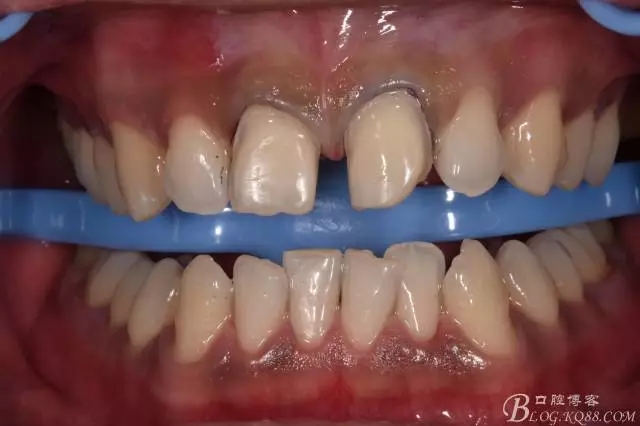

640.webp (2).jpg

640.webp (3).jpg

備完后拋光